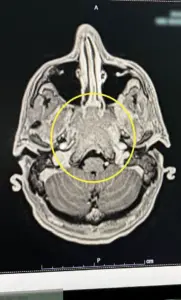

The diagnosis that followed was both shocking and rare: Nasopharyngeal Small Cell Neuroendocrine Carcinoma (NPC), a type of cancer so uncommon that only 17 cases have been reported over the past two decades.

The prognosis was sobering; McNamara’s oncologist informed him that his chances of survival were roughly fifty-fifty, given the tumor’s location in the sinuses rather than its usual habitat in the lungs.

This diagnosis has spurred a rigorous course of treatment involving chemotherapy and proton beam therapy, which have managed to reduce the size of the malignant mass.